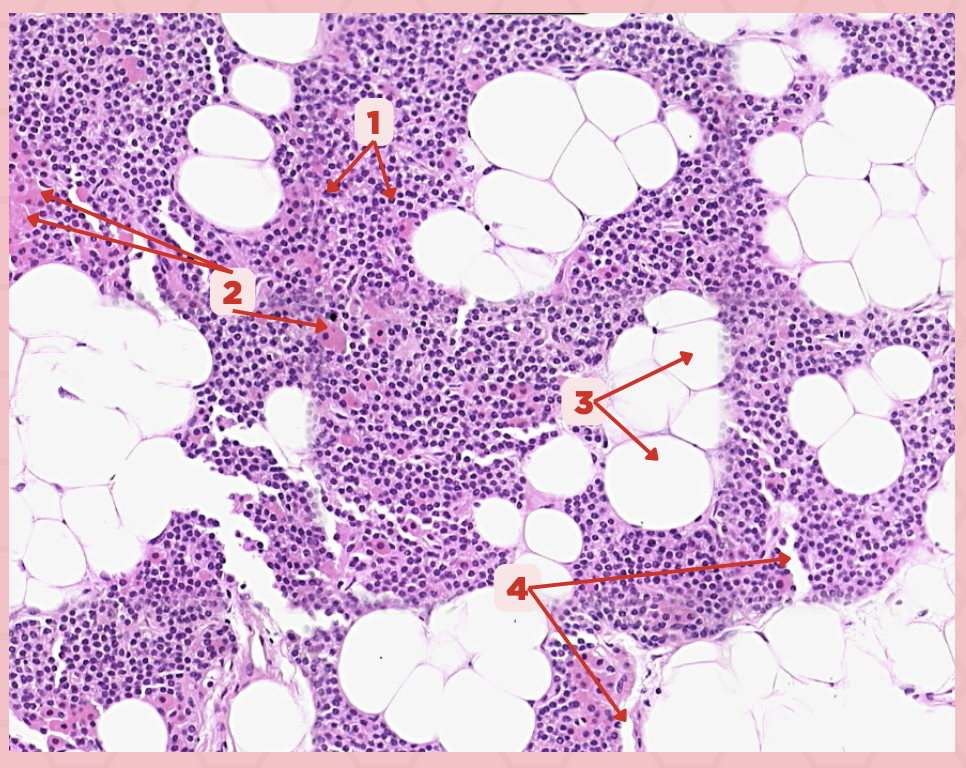

The parathyroid gland is divided into _____, packed with epithelial cells that form cords and clusters.

False

TRUE or FALSE. The parathyroid gland is only enveloped by its own thin connective tissue capsule.

Parathyroid Capsule

Identify the structure labeled as 1.

Lobules

Identify the structure labeled as 2.

Septa

Identify the structure labeled as 3.

Parathyroid

Identify the specimen.

Parathyroid

Identify the specimen.

Parathyroid

Identify the specimen.